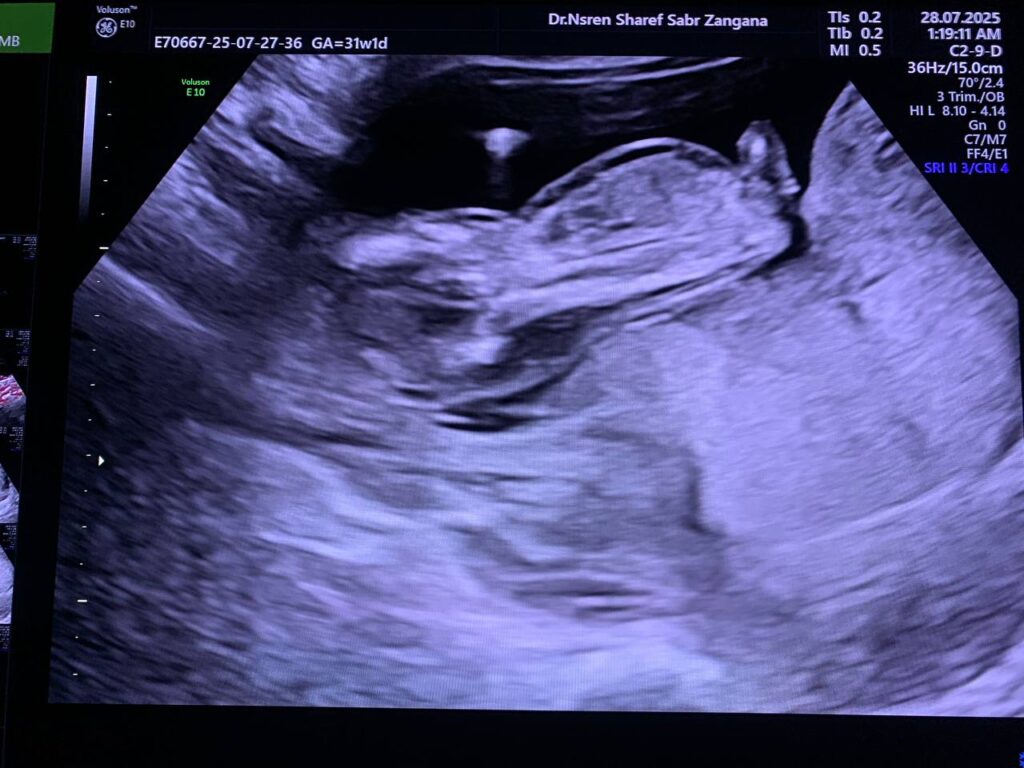

Diffuse edema with Increase nuchal translucency 6.7mm , hypoplastic nasal bone , picture mostly of hydrops fetalis with chromosomal anomaly , please for further study

CRL= 12w+6d